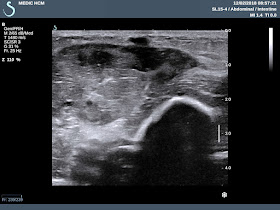

Ultrasound of abdomen

detected  one hyperechoic foreign body # 3.5 cm which penetrated  gastro-duodenum wall  to gallbladder. The  gallblader wall

is very thick # 1 cm.